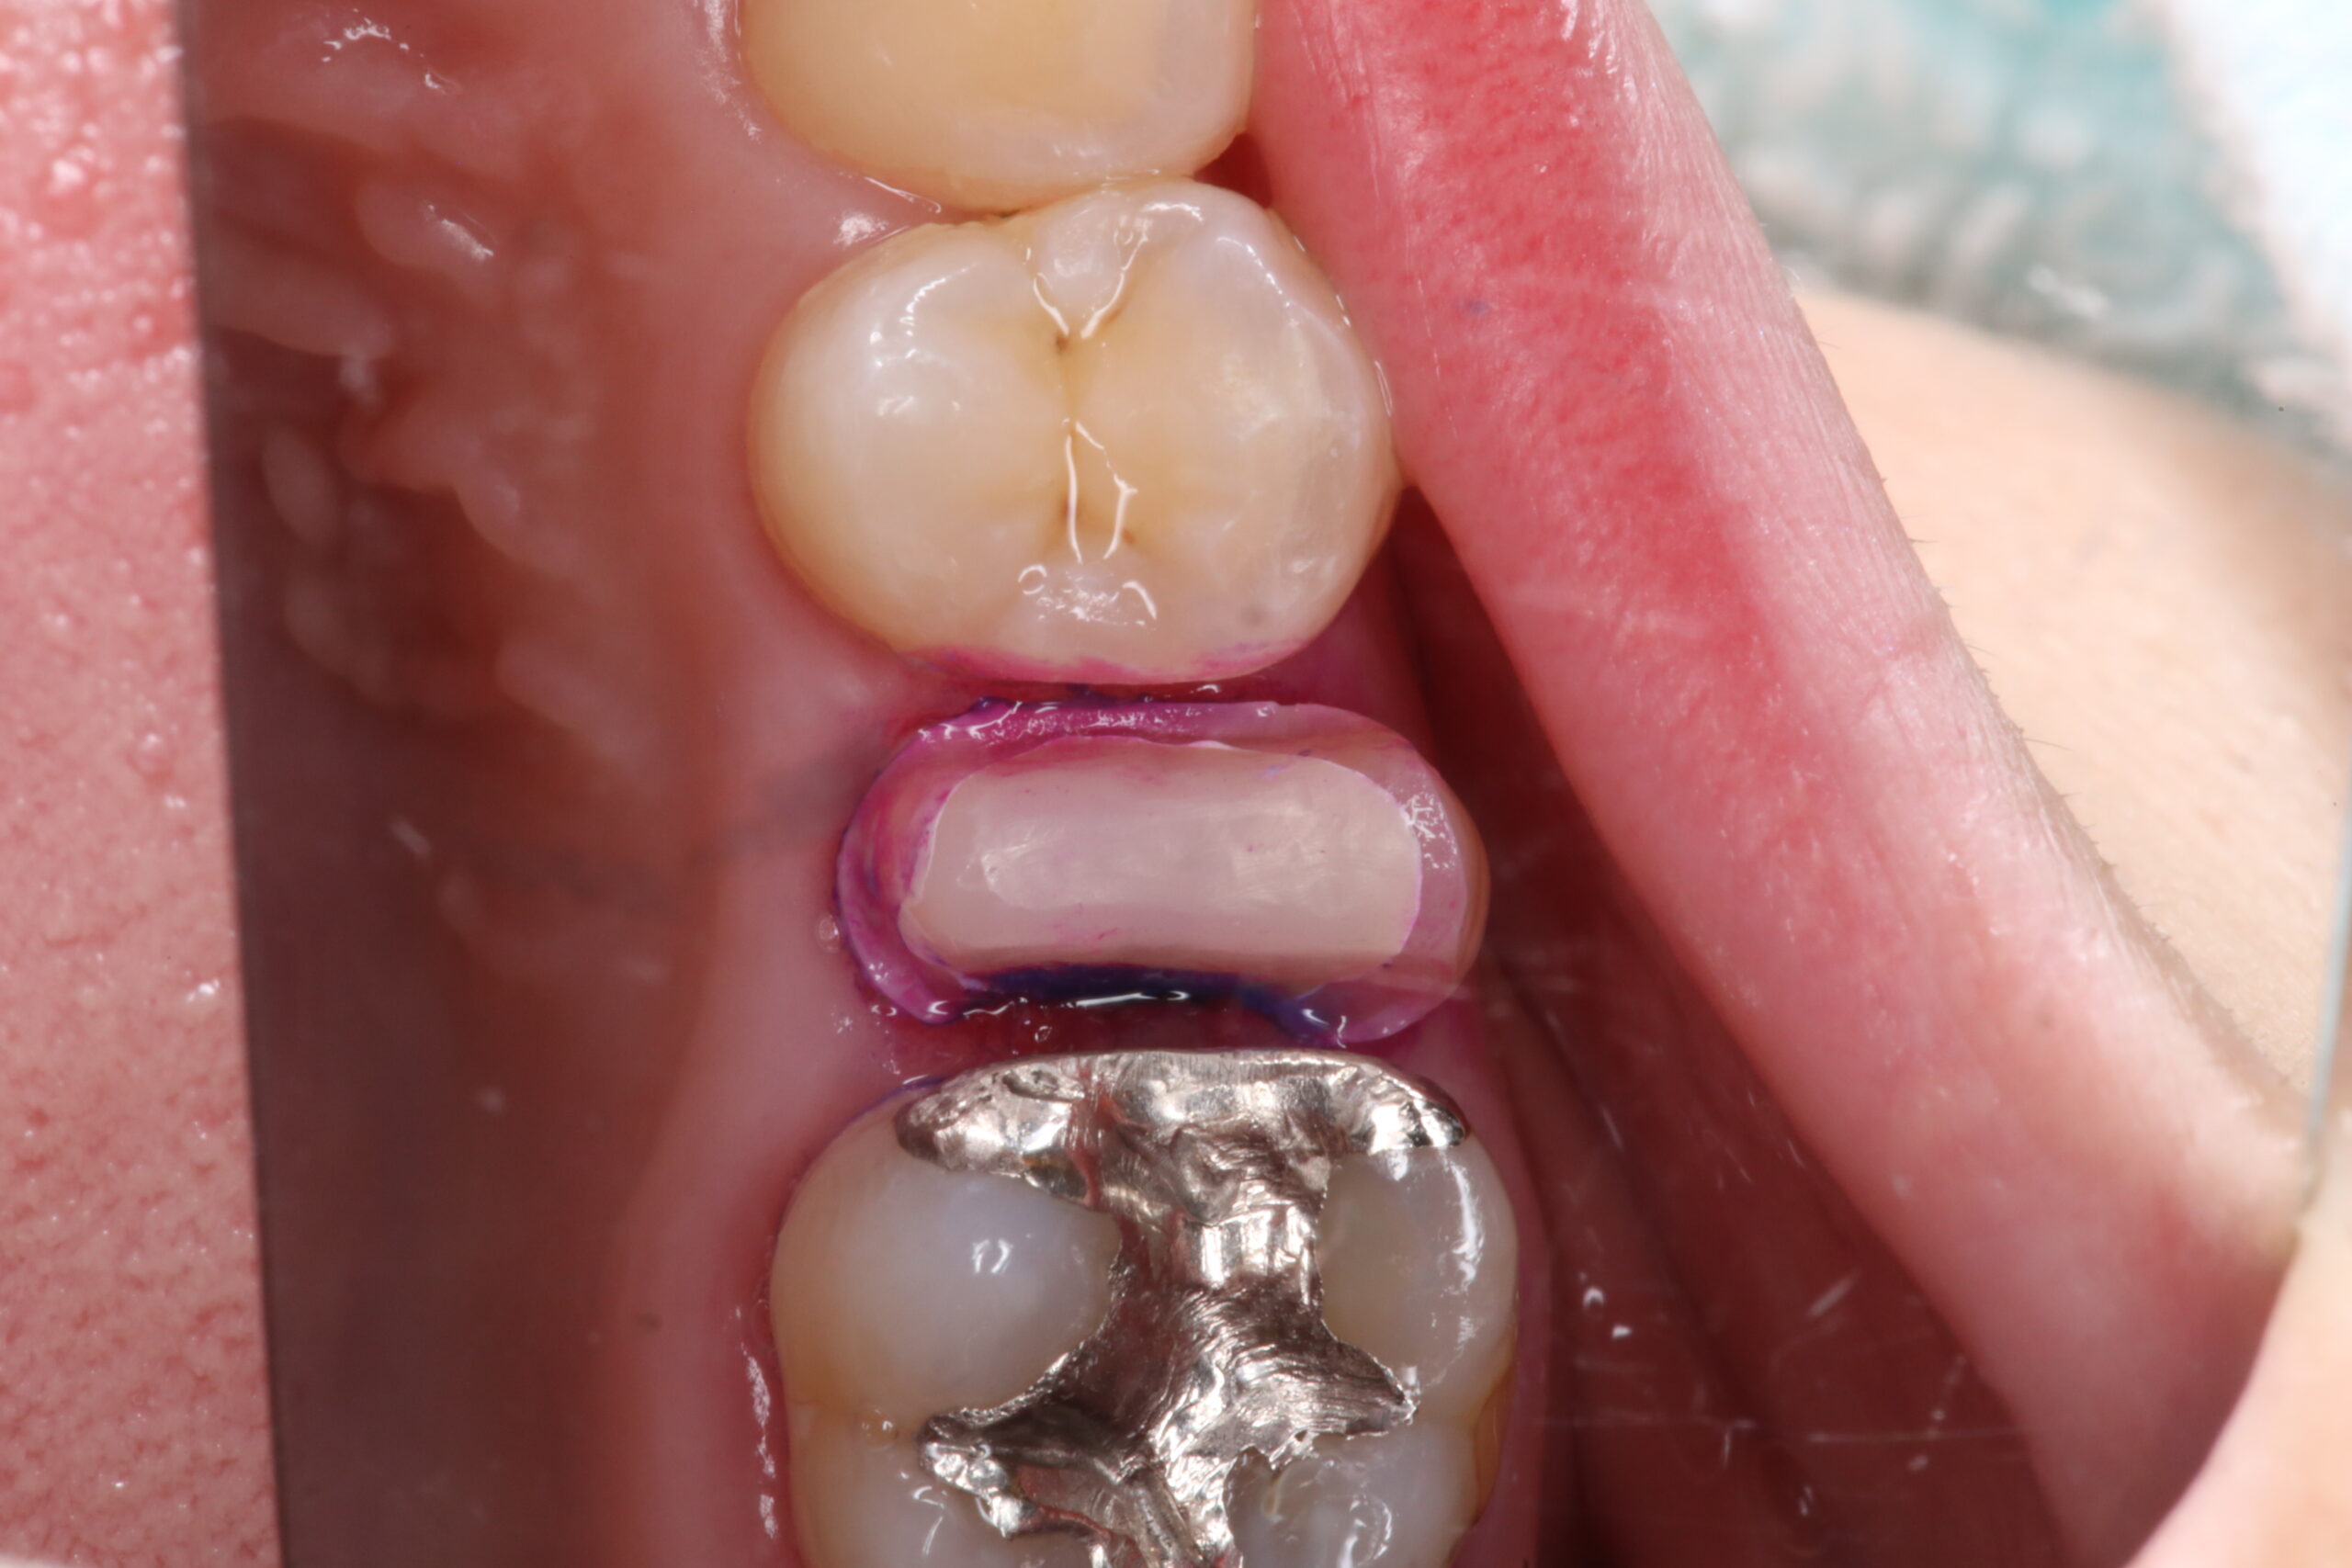

いらしていただいて、仮蓋を除去、歯に付着している汚れを染め出した状態です。

しっかり汚れを除去しました。

歯茎が若干炎症し、出血しているのがわかります。

この状態ではセラミックを100%安全に設置することはできません。

麻酔をして、ラバーダム、フロスリガチャーを行い、セラミックをセットする準備を行います。